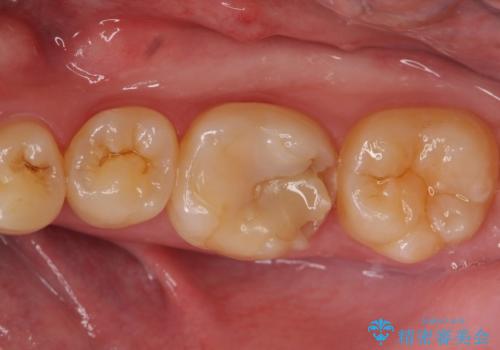

- 左下6の歯が欠けてしまったので診て欲しいといらっしゃった方の症例です。

虫歯除去後、オールセラミッククラウンによる補綴を行いました。